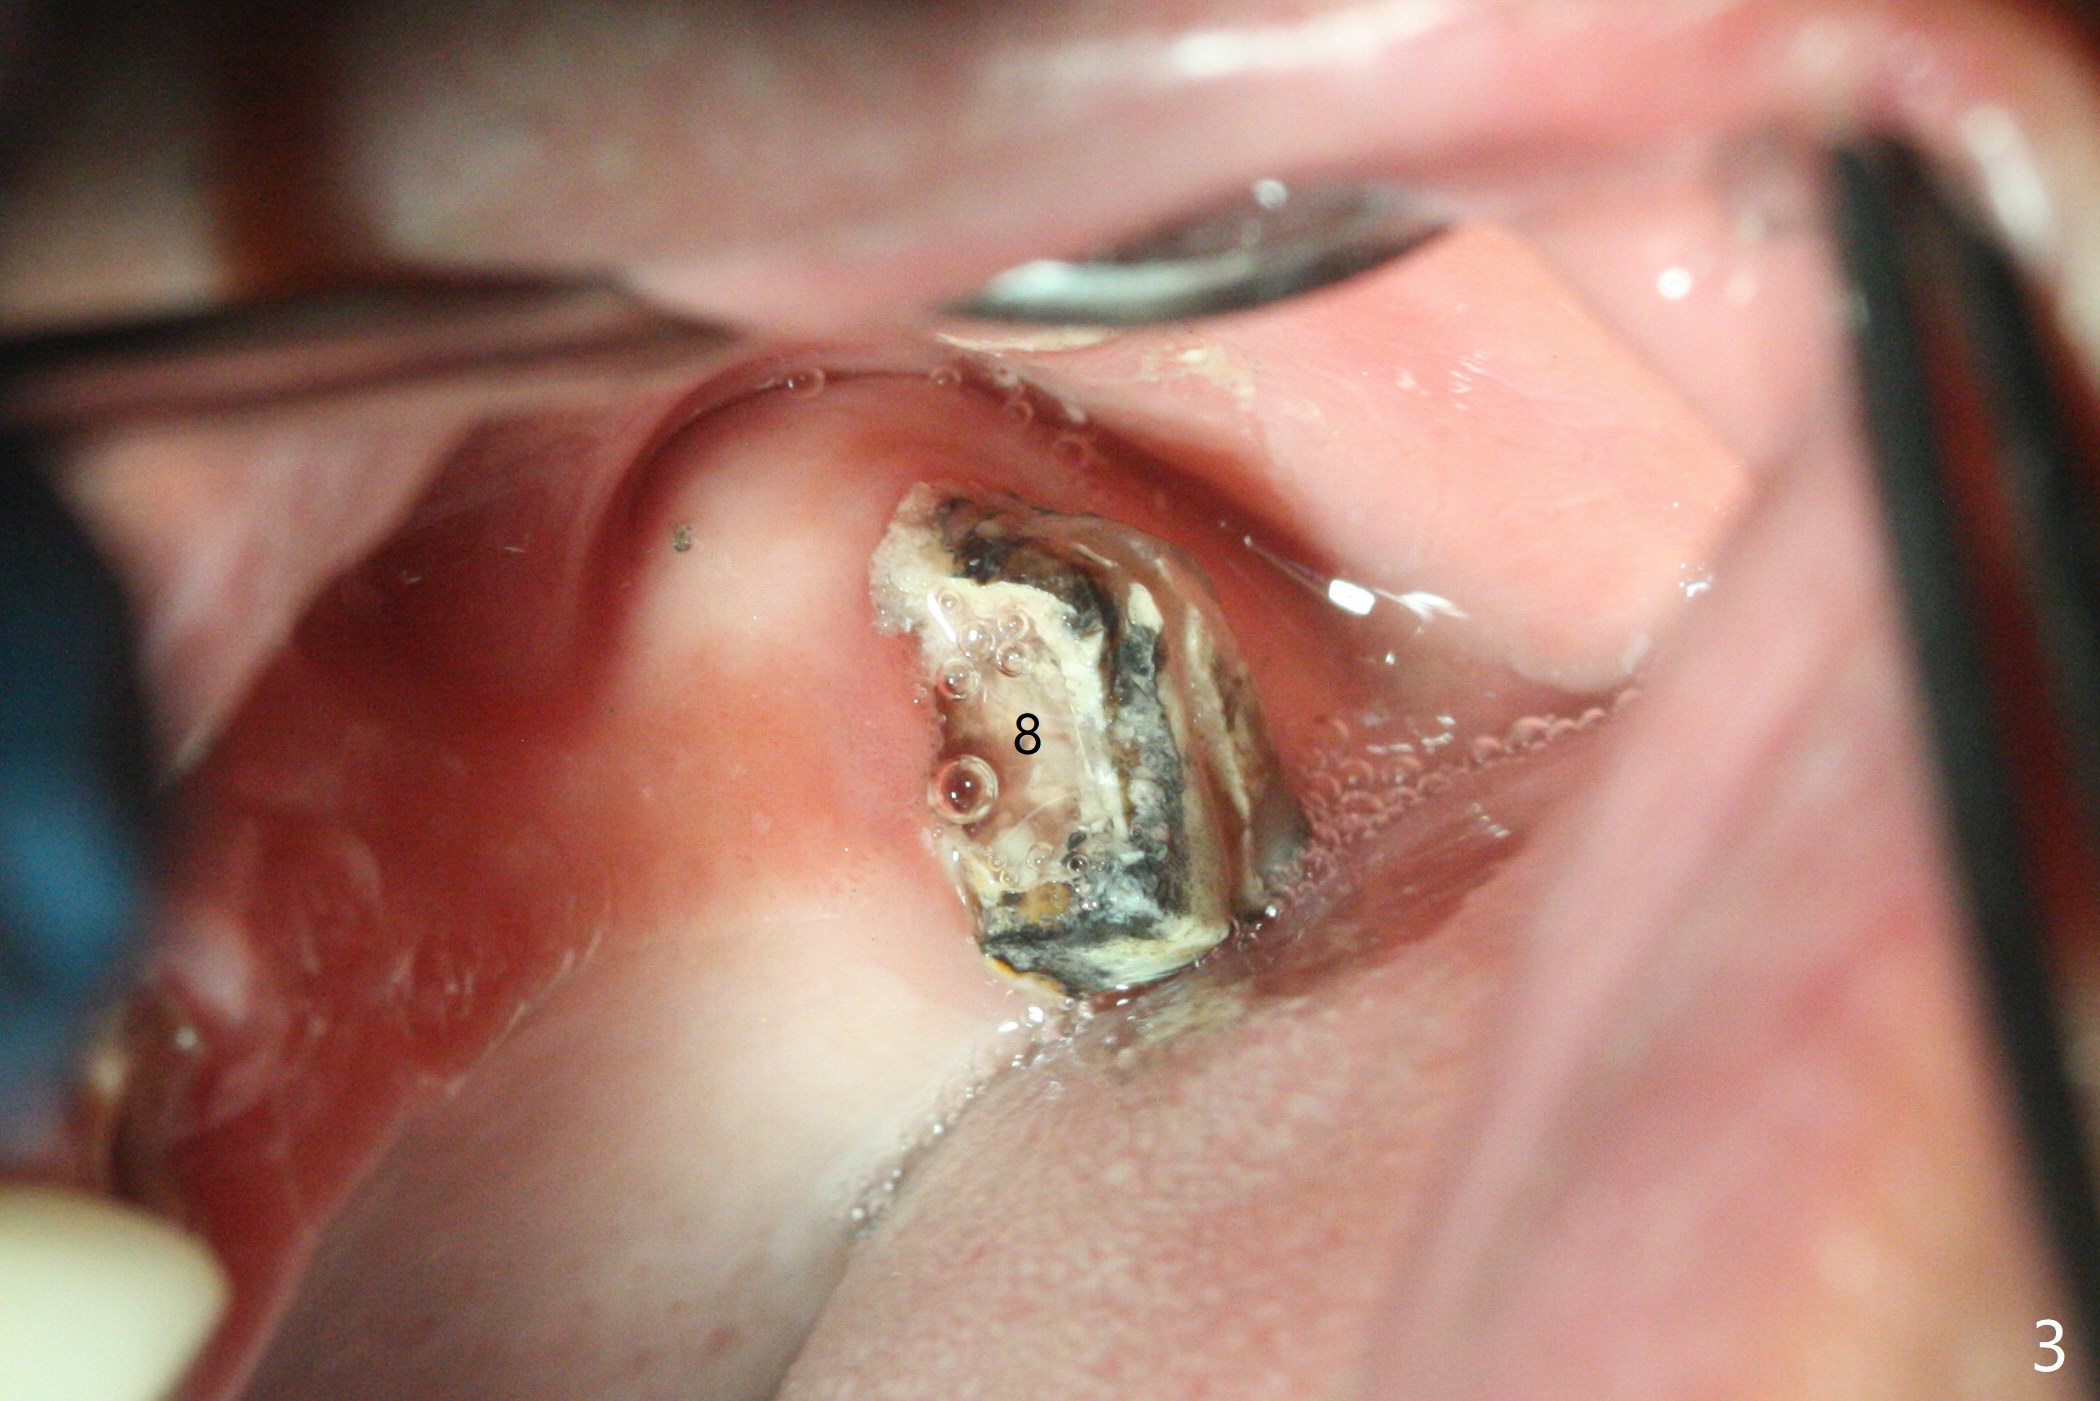

为了美观,病人希望先进行下颌治疗,当他回来时,提到左上肿胀,但是没有明显疼痛。去除左上4-8桥,发现4仍可以保留(图一,二),8龋齿龈下(图三)。4根管治疗只发现颊侧根管(图四:B),腭侧根管好像闭锁,与CT一致。放置氢氧化钙糊剂,明天病人回来治疗,术后两周。我的疑问是,如果肿胀消失,仅完成颊侧根管充填,治疗够吗?什么时候可以安置球状牙桩?如果肿胀没有消失,怎么搞通腭侧根管?